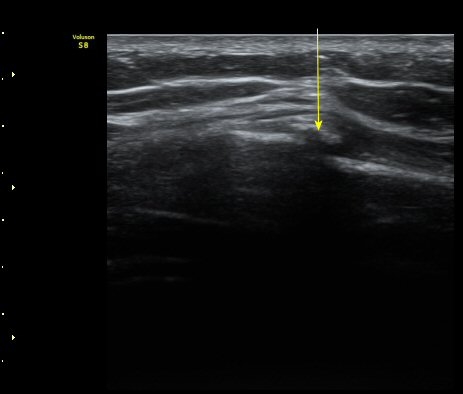

ÃÊÀ½ÆÄ °Ë»ç

¹Ì¼¼ÇÏ°Ô °¥ºñ»À ÇÇÁú°ñ ¿¬°á¼º ¼Ò½Ç°ú ¿¬ºÎÁ¶Á÷ ºÎÁ¾ÀÌ °üÂûµÊ(loss of cortical continuity and soft tissue swellingof rib)   »çÁø 1, 2, 3

3, 4,, 5 ¹øÂ° °¥ºñ»À °ñÀýÀÌ È®ÀεÊ.